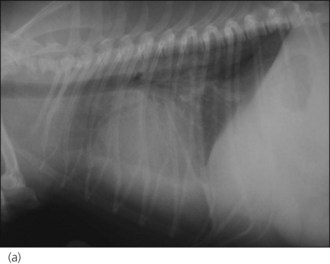

The dog was suitably compliant (a gentle giant!) so thoracic radiographs were taken to look for evidence of CHF and evaluate the size of the cardiac silhouette (Figure 31.2). The dog was subsequently started on furosemide (2 mg/kg p.o. q 12 hr) and digoxin (0.1 mg/m2 p.o. q 12 hr) and referral arranged to a cardiologist for echocardiography and implementation of further management. This confirmed the suspicion of DCM with left atrial enlargement and pimobendan (0.125 mg/kg p.o. q 12 hr, 1 hour before feeding) and benazepril (0.25 mg/kg p.o. q 24 hr) were dispensed. The dog’s ventricular response rate had reduced to 160 beats per minute when he was seen at the referral centre (5 days after digoxin was commenced) and additional antidysrhythmic therapy was not therefore indicated.

Figure 31.2 (a) Right lateral and (b) dorsoventral thoracic radiographs of a dog with dilated cardiomyopathy and mild pulmonary oedema. Peribronchial infiltrates are present throughout the lung, with patchy alveolar infiltrate in the caudoventral lung field.